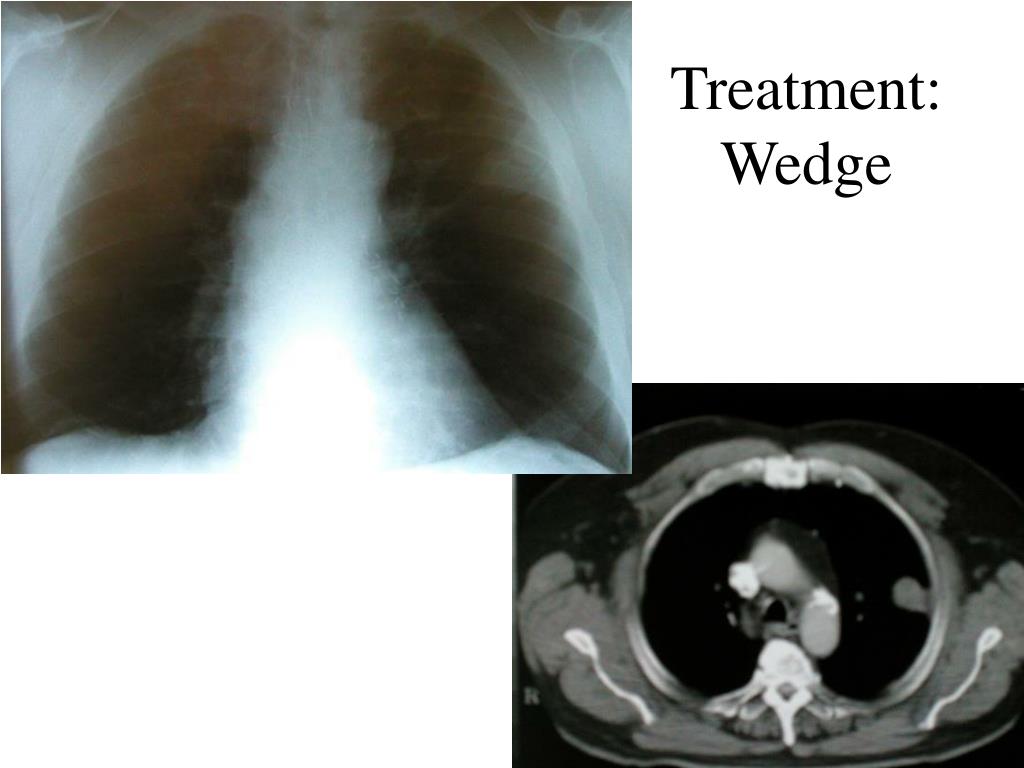

PPT - Surgical Management Of Lung Cancer PowerPoint Presentation, Free

PPT - Surgical Management of Lung Cancer PowerPoint Presentation, free www.slideserve.com

lung surgical cancer management ppt powerpoint presentation wedge treatment